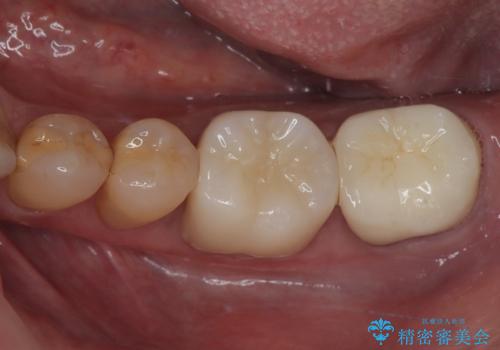

下顎大臼歯の再根管治療とオールセラミッククラウンによる補綴治療

奥歯がうずく